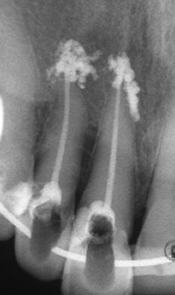

Запълване с препресване

Ендодонтия